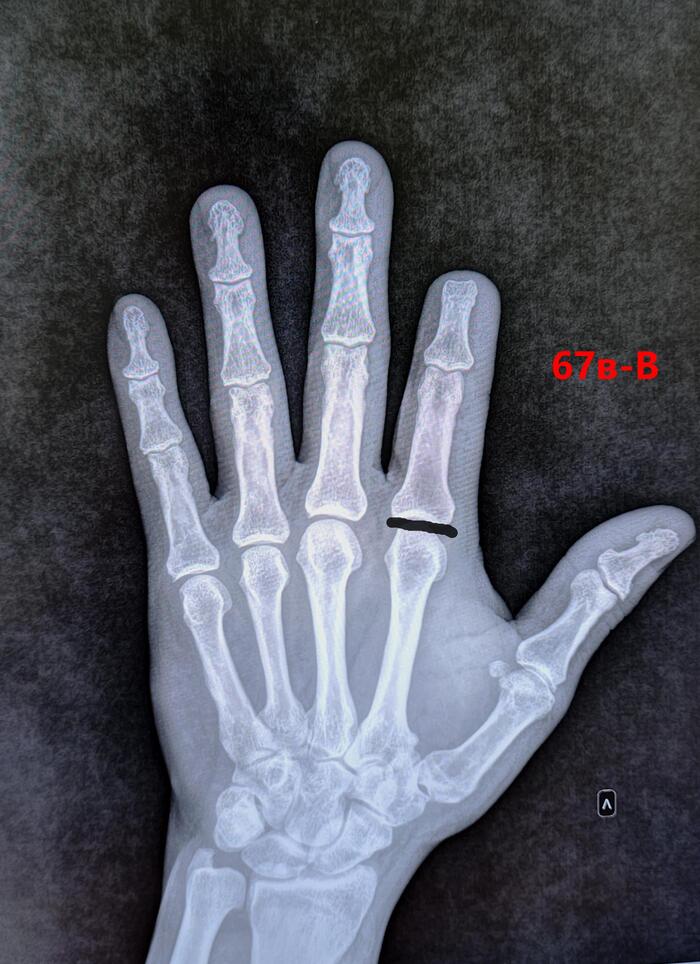

У выше представленного призывника, при измерении истинной длины нижних конечностей, выявлено укорочение правой нижней конечности на 2.5 см., что соответствует ст.69в-В(ограниченно годен к в/сл)